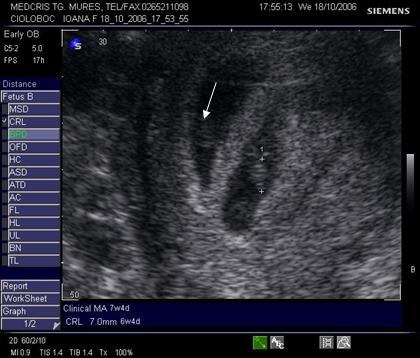

Fig nr 42 Sarcina

12 sapt. biamniotica bichoriala, semnul lambda ( cu sageata )